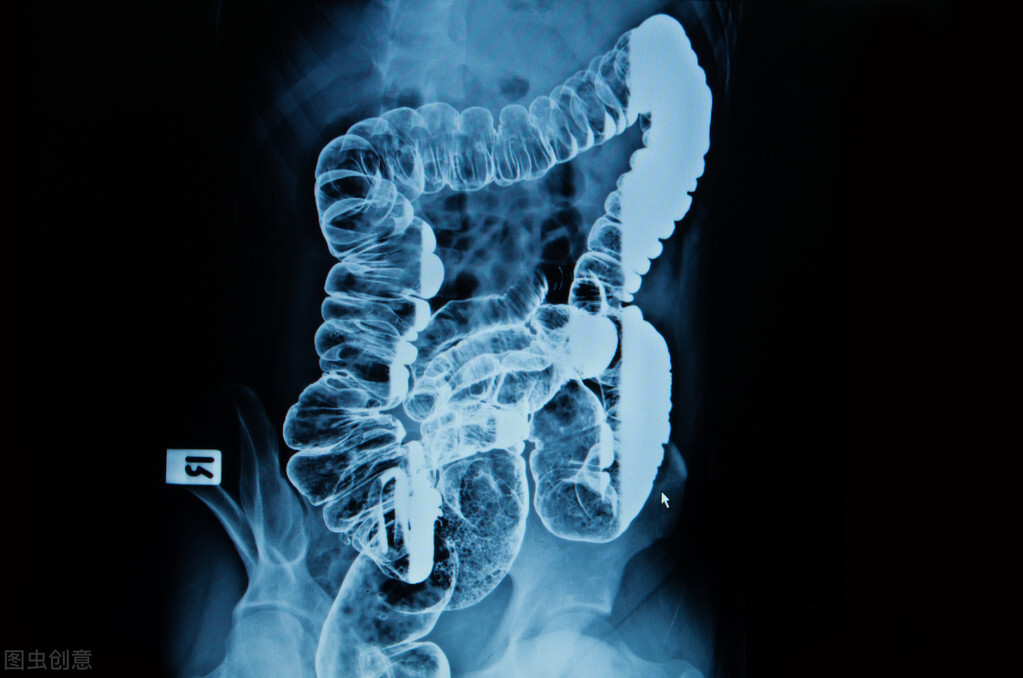

第四,癌症。肛门附近如果发生癌症,也会导致潮湿瘙痒,最近的有肛门癌、直肠癌等,早期可能表现为粘液分泌增多,中晚期可能会出现癌灶破裂出血、分泌液体,然后会不断刺激肛周,引发潮湿、瘙痒。

一些肠癌也会导致肛周的潮湿、瘙痒,需要格外注意。